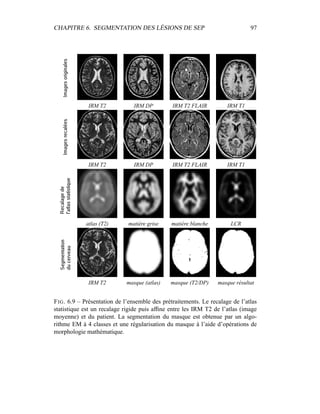

c’est donc sur elle que portera l’analyse lors de la segmentation en tissus et de la

présentation du modèle de volume partiel. Les autres modalités seront utilisées a

posteriori.

4.4 Segmentation en tissus.

4.4.1 Algorithme

Le but de cette segmentation en tissus sains est leur caractérisation, afin de

pouvoir construire un premier processus de détection des lésions de SEP. Même

si les 4 séquences (T2 FSE / DP, T1, T2 FLAIR) sont disponibles, la segmenta-

tion ne sera menée dans un premier temps que sur le couple T2/DP, alors que les

autres séquences – T1, T2 FLAIR – montreront tout leur intérêt pour la détection

des lésions et leur spécification : ceci permet de n’effectuer la segmentation que

sur des images vierges de tout rééchantillonnage. En outre, nous ferons délibéré-

ment l’impasse sur certains processus décrits dans la littérature pour améliorer la

qualité visuelle de la segmentation – les contraintes sur le voisinage, par exemple

– puisque notre but est d’obtenir un critère sur l’intensité qui sera raffiné ensuite

par contraintes spatiales.

Dans sa formulation la plus simple, le processus de segmentation prend un

ensemble multi-séquences à segmenter – les deux images T2 / densité de pro-

tons, auxquelles le masque binaire du cerveau a été appliqué – et fournit en sortie

3 labélisations : matière blanche, matière grise, LCR. Comme indiqué dans les

CHAPITRE 4. SEGMENTATION EN TISSUS 53

équations 4.10 et 4.11, l’algorithme EM donne deux grands résultats :

– la labélisation des segmentations via les γk

i

– l’estimation des paramètres du modèle µk et Σk.

4.4.2 Présentation des résultats

Pour éliminer dans un premier temps l’influence des lésions de SEP, un témoin

a été choisi pour cet exemple, et les résultats sont présentés dans la figure 4.5. Pour

la segmentation du masque du cerveau, seule la segmentation était intéressante.

Une mauvaise estimation des paramètres de classes, ou un mauvais modèle était

sans importance tant que la segmentation était valide. Par contre, dans le cas de la

segmentation en tissus, avoir une bonne estimation des paramètres est primordial,

car c’est à partir de là que les lésions de SEP vont être segmentées. Pour obser-

ver la qualité de la segmentation dans la figure 4.5, il faut donc en permanence

regarder deux espaces reliés.

– L’espace des intensités : visualisé via l’histogramme conjoint entre les deux

modalités, il est représenté par les paramètres de classes µk et Σk. Une mé-

thode pour visualiser ces paramètres est de tracer l’estimateur de confiance

donné par p(Z = z) = cte. Dans un espace 2D, cet estimateur est en fait

l’ellipse de Mahalanobis donné par 1

2

(X − µk)T

Σ−1

k (X − µk) = λ. Dans

toutes les figures similaires à la figure 4.5, les ellipses vérifieront λ = 1.

Pour avoir une meilleur visibilité de l’histogramme, celui-ci est en fait un

log-histogramme : la couleur de chaque pixel de l’image correspond au log

du nombre d’occurences du couple (IT2, IDP ) correspondant dans le couple

d’image IRM T2 / IRM DP. Ceci permet essentiellement de visualiser sur

le même histogramme le LCR avec le reste des tissus, bien que le nombre

de voxels correspondant au LCR soit très faible.

– L’espace des images, dans lequel les segmentations sont effectivement vi-